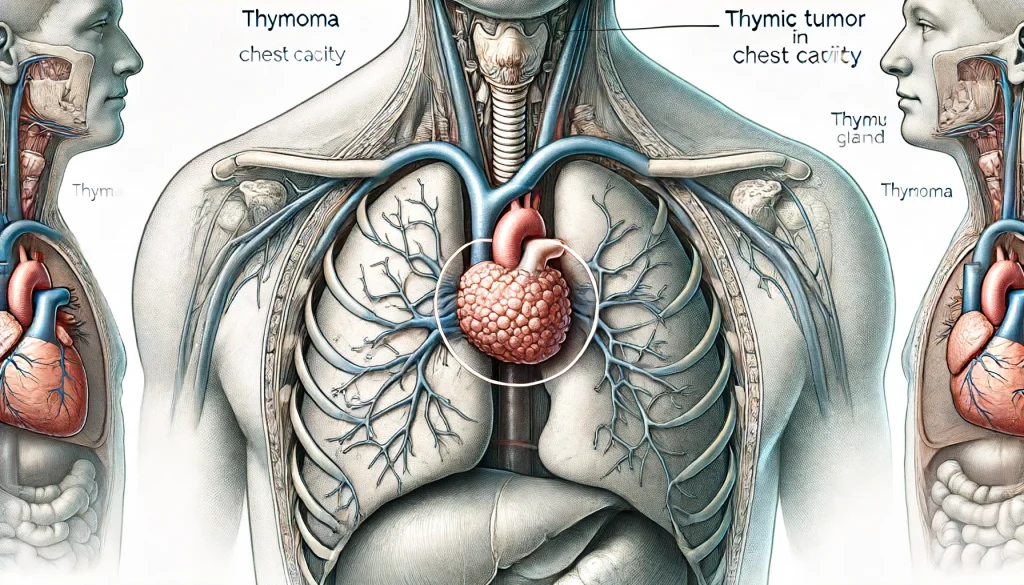

一般撮影|大阪母子医療センター, 胸腺腫(きょうせんしゅ Thymoma) – 呼吸器疾患 - 神戸きしだ,

胸腺腫(きょうせんしゅ Thymoma) – 呼吸器疾患 - 神戸きしだ, 一般撮影|大阪母子医療センター,